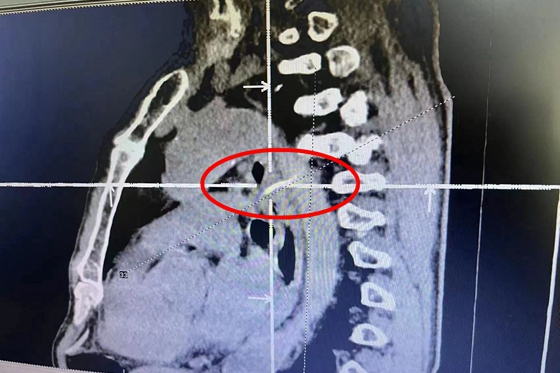

张大爷在家人的陪伴下来到湘雅常德医院,在完善食道 CT 及 CTA检查后提示:异物已经穿破食管并刺到降主动脉管壁。患者在转运过程中随时可能出现主动脉破裂、纵隔感染等问题而危及生命,情况紧急,医护人员马上为张大爷准备轮椅,禁食休息。

在取得患者及家属同意后,当日立刻为患者进行急诊手术,术中见食管内一弓形鱼刺卡顿,左侧穿出食管壁,可见明显搏动。

术中,顺利取出异物,并置入胃管。术后,患者胸痛缓解,病情平稳,患者康复中。